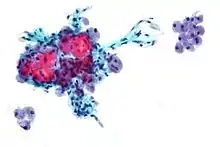

It is difficult to correctly diagnose follicular neoplasms (FNs) on fine-needle aspiration cytology (FNAC) because it shares many cytological features with other mimicking lesions.[5]

It is impossible to distinguish between follicular adenoma and carcinoma on cytological grounds. If fine needle aspiration cytology (FNAC) suggests follicular neoplasm, thyroid lobectomy should be performed to establish the histopathological diagnosis. Features sine qua non for the diagnosis of follicular carcinoma are capsular invasion and vascular invasion by tumor cells. Still, focuses of the capsular invasion should be carefully evaluated and discriminated from the capsular rupture due to FNA penetration resulting in WHAFFT (worrisome histologic alterations following FNA of thyroid).